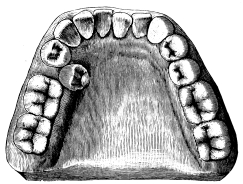

There is an abnormality of the upper molars which may with advantage be mentioned here. In this deformity the posterior buccal root is situated in a plane much internal to the anterior—in other words, it is an exaggeration of the normal arrangement. Such teeth have been termed by Mr. Booth Pearsall “oblique rooted” (fig. 21). The abnormality is met with most frequently in the third molar, sometimes in the second, rarely in the first. The difficulty encountered in extracting these teeth is{27} that the outer blade of the forceps tends to slip round. Oblique-rooted teeth can at times be diagnosed by noting an undue prominence of the alveolus over the anterior buccal root, and are best removed with forceps similar to that shown in fig. 20.